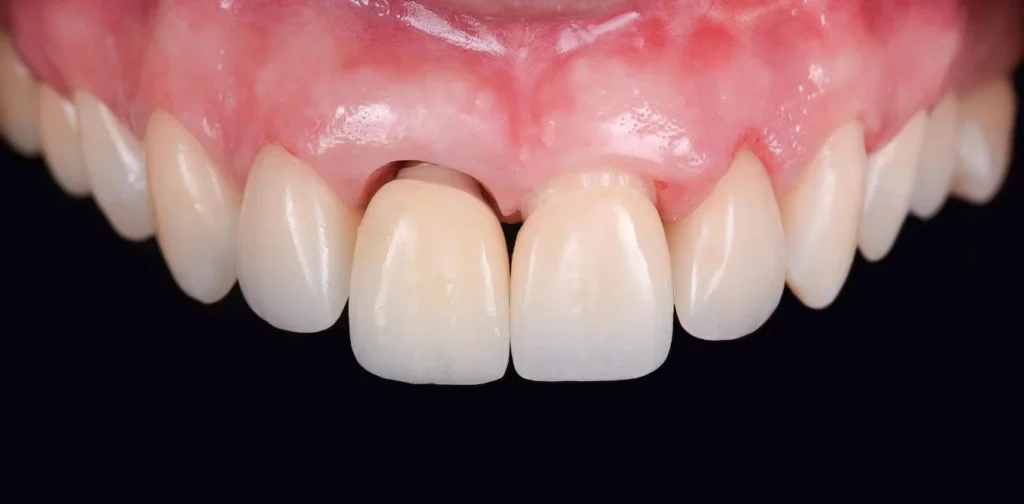

First aesthetic advantage: Optimal gingival and periodontal aesthetics.

Using Healing Customized to shape and reconstruct periodontal tissue, together with Customized Abutment for contouring, allows the personalized implant tooth to have gingival contours that mimic natural teeth, providing superior “pink aesthetics” compared to traditional implant restorations.

Step 2: Placement of customized healing abutment to shape periodontal tissue.

The customized healing abutment is usually placed immediately during implant placement. In some cases where there is insufficient bone or gingival volume, Healing Customized may be placed after 2 months, once the implant has integrated.

Feature 2: Reconstruction of gingiva and periodontal tissues according to anatomical standards using Healing Customized.

Periodontal tissue surrounding the tooth is extremely important. Biologically, periodontal tissue connects to the tooth through ligaments and junctional epithelium, forming a biological barrier that prevents bacteria from penetrating deeper. Aesthetically, periodontal tissue creates soft curved contours (known as pink aesthetics), contributing to the uniqueness of each person’s smile.

When a tooth is lost, the surrounding periodontal tissue collapses. With older methods using prefabricated abutments, it is very difficult to regenerate periodontal tissue.

With the personalized implant solution, the healing abutment is custom manufactured by simulating the ideal periodontal morphology for each tooth and each patient. Regenerating periodontal tissue according to anatomical standards helps future implant teeth appear more aesthetic, more biological, and more natural in function.